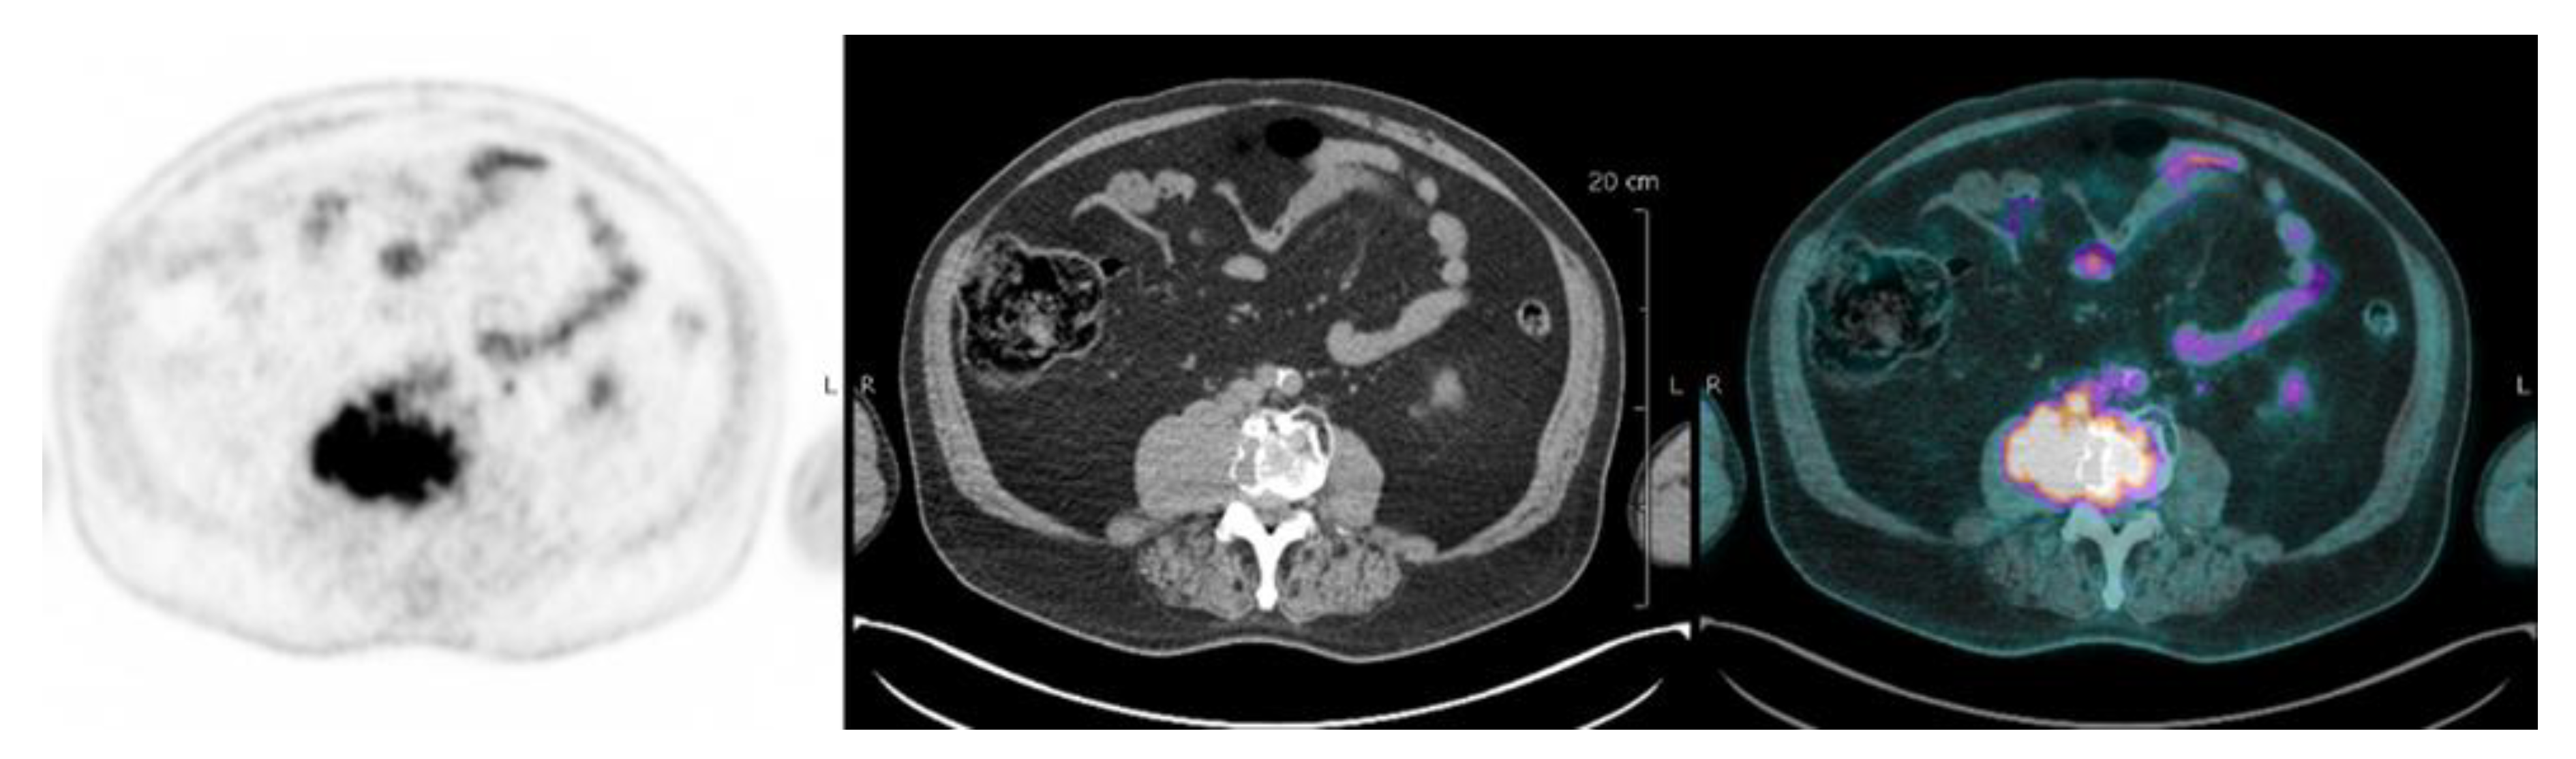

| Focal lesion | Foci of uptake above the surrounding background noise on two successive sections with or without osteolysis on the CT image | Suggested as pejorative prognostic biomarker using cut off 3. | Bartel et al., 2009 [8] |

| EMD | Tissue invasion without contiguous bone involvement. | Presence of EMD suggested as pejorative prognostic biomarker | Zamagni et al., 2011 [9] |

| PMD | Soft tissue invasion with contiguous bone involvement. | Presence of PMD suggested as pejorative prognostic biomarker | Moreau et al., 2019 [19] |

| Diffuse medullary involvement | Homogenous diffuse uptake of the pelvic-spinal-peripheral skeleton higher than the liver background. | Prognostic value currently not demonstrated | |

| FL SUVmax | Maximal SUVmax of bone focal lesions | Suggested as pejorative prognostic biomarker using cut off of 4.2 | Zamagni et al., 2011 [9] |

| FDG-PET/CT abnormality | Presence of Focal lesion(s) and/or EMD lesion(s) and/or PMD lesion(s) and/or diffuse medullary involvement. | Absence of FDG-PET/CT abnormality considered as a favourable prognostic | Rasche et al., 2017 [16] |